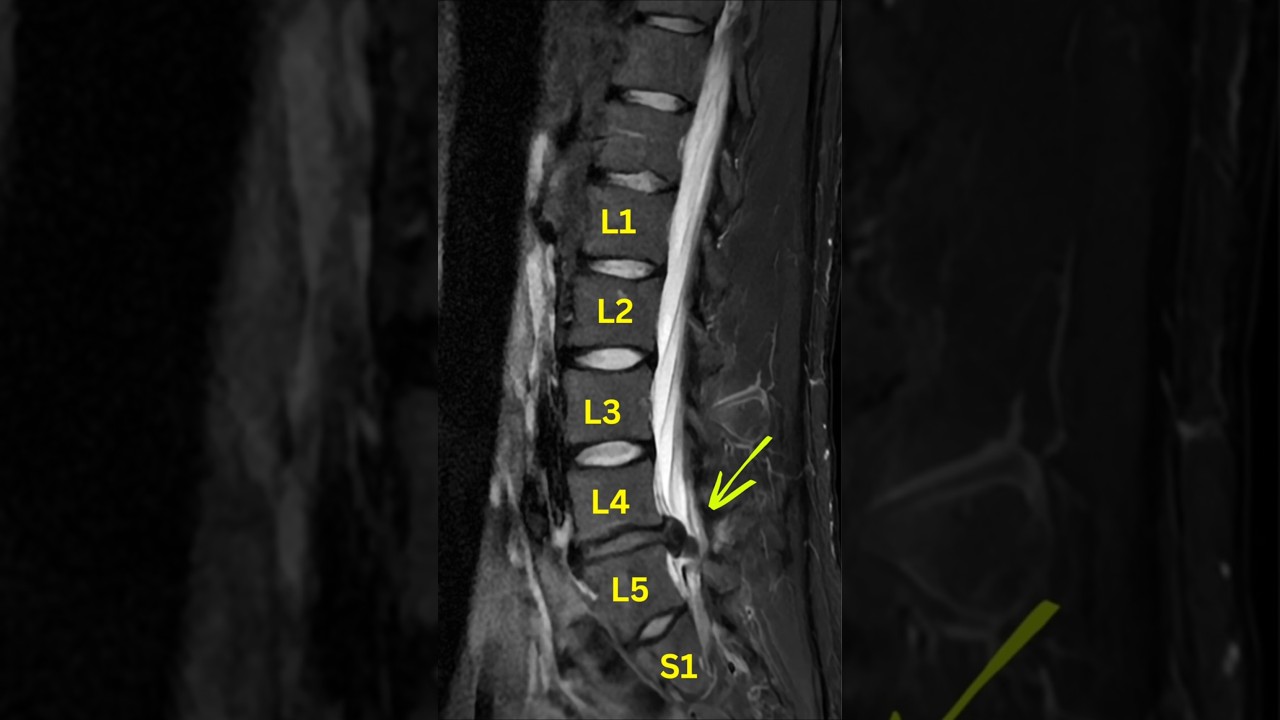

How to fix Lumbar Disc Extrusion

Lumbar Disc Extrusion ≠ Surgery by Default 🚫🔪

A lumbar disc extrusion sounds alarming—but in many cases, the body has a strong capacity to heal when the spine is loaded progressively and intelligently 🧠🏋️‍♂️

MRI findings must always be matched with symptoms, movement, and function 🧩